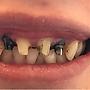

[請益] 四顆門牙做單顆牙套還是牙橋?(有圖慎入)

[ teeth_salon ]15 留言, 推噓總分: +2

作者: sihyu - 發表於 2017/11/13 17:43(8年前)

4Fdontlearn: 我偏好4顆單顆牙套, 較好清潔11/15 00:53

6Fdontlearn: 要看殘留牙齒的量,一般不會很容易就掉下來11/15 13:48

14Fdontlearn: 這就看你決定了吧, 一顆一顆做衛生比較好維持, 牙橋11/18 00:50

15Fdontlearn: 比較不容易斷,各有優缺11/18 00:50